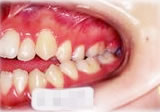

開咬症例

初診時年齢○○歳。前歯部での咬合不全を主訴に来院。

骨格性開咬と診断し、外科的処置を併用して治療。

矯正治療は上下顎歯列を拡大しスペースを作成、非抜歯にて行った。

右側面 右側面 右側面

左側面 左側面 左側面